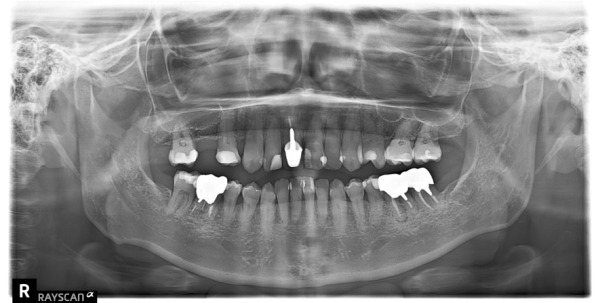

お口の中を拝見したところ、右上5・6が無く、右上4も下の歯とは噛んでいない状態でした。このことから、右側の噛み合わせが不安定なため、痛みが生じていることがわかりました。

1日目 レントゲン写真撮影後、虫歯の有無、歯周病の検査、歯石除去を行いました。治療計画のため、上下の歯型を取りました。

センター南デンタルクリニックでは、エックス線画像や口腔内写真から、患者様のお口の中で、『どういう状態なのか、なぜそうなったのか』原因を知っていただくために、歯型を取り、お口全体の話をさせていただいています。